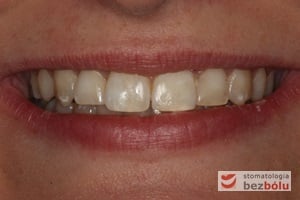

Pacjentka lat 22 zgłosiła się do naszej placówki celem podjęcia leczenia ortodontycznego. Głównym oczekiwaniem pacjentki była poprawa estetyki uśmiechu oraz brak ekstrakcji zębów na drodze do jej uzyskania. Ze względu na liczne stłoczenia zębów w górnym i dolnym łuku, dość duży materiał zębowy w porównaniu z bazą kostną, a także zgryz przewieszony boczny prawostronny po dokładnej analizie cefalometrycznej oraz analizie modeli diagnostycznych zastosowano leczenie bezekstrakcyjne z wykorzystaniem strippingu jako alternatywy dla usuwania zębów, mającego na celu uzyskanie miejsca w łuku na uszeregowanie zębów. Po fazie aktywnego leczenia trwającego 18 miesięcy zastosowano leczenie retencyjne w postaci szyny retencyjnej w łuku górnym oraz retainera stałego w łuku zębowym dolnym klejonego od kła do kła.